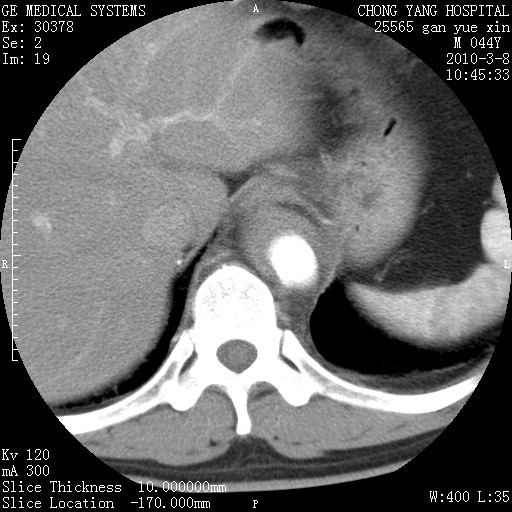

标题: CT24940:主动脉增强,典型病例。 [打印本页]

标题: CT24940:主动脉增强,典型病例。

夹层动脉瘤。

动脉夹层

夹层动脉瘤,典型

主动脉夹层。

动脉夹层的分型:

⒈debakey分型:根据主动脉夹层累及部位,分为三型:ⅰ型:原发破口位于升主动脉或主动脉弓部,夹层累及升主动脉、主动脉弓部、胸主动脉、腹主动脉大部或全部,少数可累及髂动脉。ⅱ型:原发破口位于升主动脉,夹层累及升主动脉,少数可累及部分主动脉弓。ⅲ型:原发破口位于左锁骨下动脉开口远端,根据夹层累及范围又分为ⅲa,ⅲb。ⅲa型:夹层累及胸主动脉。ⅲb型:夹层累及升主动脉、腹主动脉大部或全部。少数可累及髂动脉。

⒉stanford分型:a型:夹层累及升主动脉,无论远端范围如何。b型:夹层累及左锁骨下动脉开口以远的降主动脉。

夹层动脉瘤,少量胸水

夹层动脉瘤;左侧少量胸腔积液。

典型主动脉夹层。